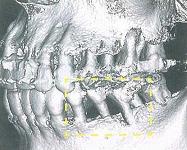

そこで当院では必要に応じて歯科専用のCT撮影を行っております。今までのパノラマエックス線写真やデンタルエックス線写真とは違い、CT画像は立体的に画像を映しだし診ることが可能です。その為、より正確な診断を行うことができるのです。

歯科CT画像